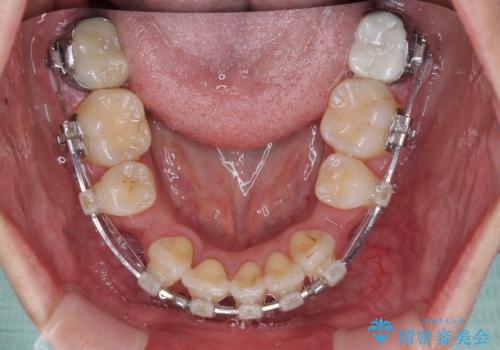

- クリアブラケット

- 2年3ヶ月

- 10-30回